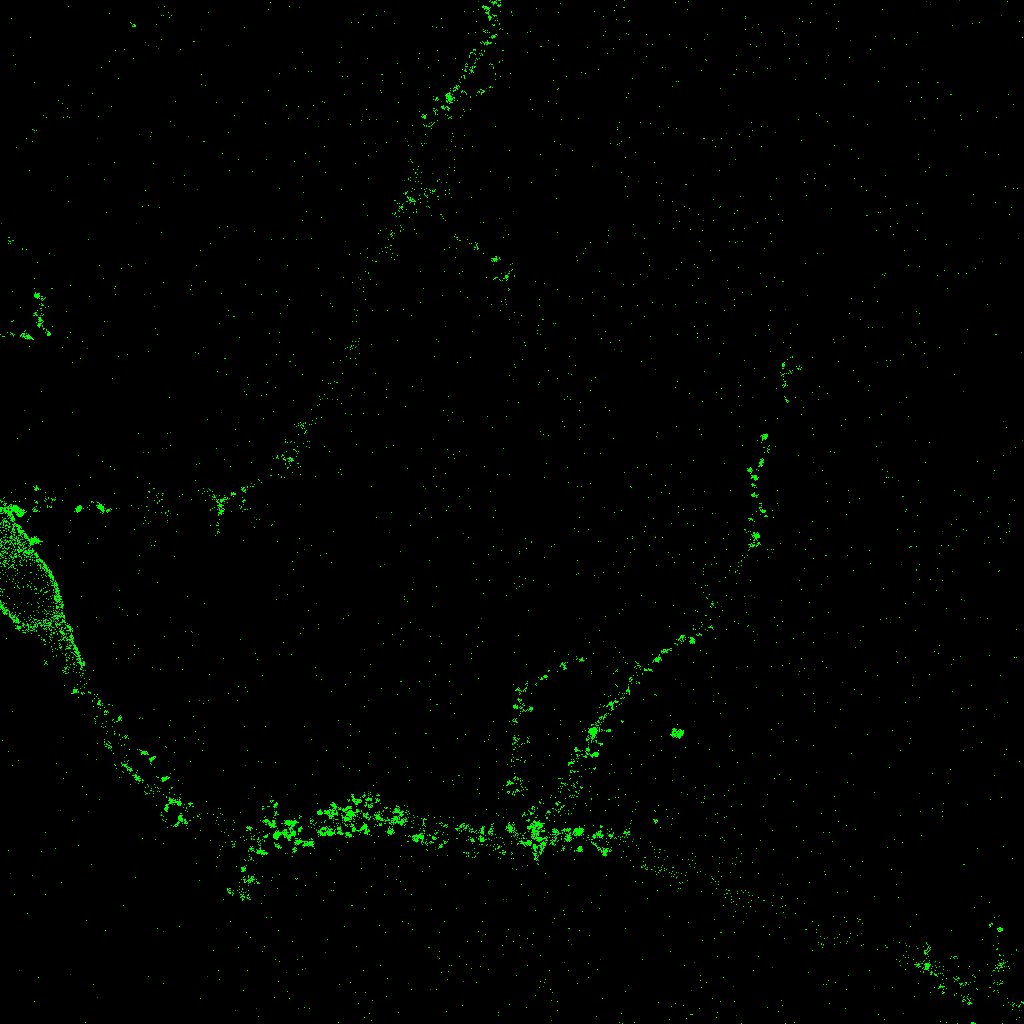

El primer plugin que desarrollamos se denomina SynapCountJ [13], y se utiliza para calcular el número de sinapsis que aparecen en la imagen de una neurona. Como ya se ha comentado anteriormente, el programa recibe dos imágenes diferentes de la misma neurona tomadas en un momento concreto tras la aplicación de dos marcadores, en rojo y verde. El usuario debe señalar manualmente la región en la que va a realizarse la medida, esto es, las distintas ramas (dendritas) de la neurona, lo que nos da una tercera imagen en azul (para esta parte hacemos uso del plugin NeuronJ [17]). Con estos datos, el programa marcará como sinapsis los puntos de rojo, verde y azul que coincidan en las tres imágenes (y que aparecerán como puntos blancos, véase la figura 1). El usuario puede modificar los parámetros introduciendo el rango tanto de rojo como de verde que considera que debe poseer una sinapsis. Según se va eligiendo el rango se pueden ir observando la zonas de la neurona que se van a marcar como sinapsis para hacer una mejor estimación. Finalmente, el programa presenta la imagen con las sinapsis señaladas y muestra también una tabla en la que se indican el número de sinapsis y la densidad obtenida. Véanse las dos imágenes de partida y el resultado dado por SynapCountJ (las tres en escala de grises) en la figura 8. En esta imagen las sinapsis corresponden a los puntos más oscuros dentro de la zona señalada.

Refer to captionRefer to captionRefer to caption

Figura 8: Resultado de SynapCountJ

Uno de los conceptos más importantes para nuestro trabajo es la noción de conexión, o más concretamente, el cálculo del número de componentes conexas. Ésta es la idea fundamental empleada para el recuento de sinapsis en una imagen de cultivo: tras solapar dos imágenes diferentes de la misma neurona en un mismo instante obtenidas tras la aplicación de dos marcadores primarios y señalar manualmente la región en la que debe realizarse la medida, las distintas sinapsis corresponden a las componentes conexas obtenidas en la intersección. El programa realiza este cálculo, marca sobre la imagen las distintas apariciones y nos da el número total de sinapsis (componentes conexas) localizadas.

Para la automatización de los procesos llevados a cabo por el grupo PSE, se planteó en primer lugar el problema del cálculo del número de sinapsis, que son los puntos de conexión entre las neuronas. Las sinapsis tienen una gran importancia en el campo de investigación tratado ya que están relacionadas con las capacidades de cálculo del cerebro, y la posibilidad de incrementar el número de contactos sinápticos puede ser una ventaja importante en el tratamiento de enfermedades neurodegenerativas. Para realizar el recuento de sinapsis se necesitan dos imágenes diferentes de la misma neurona que se obtienen usando técnicas de laboratorio, más concretamente utilizando dos marcadores que reconocen estructuras sinápticas; esas dos imágenes se superponen y se realiza el recuento de las sinapsis. En la figura 1, de tamaño 1024×1024102410241024\times 1024 píxeles, o equivalentemente 228×228228228228\times 228 micras, las sinapsis son los puntos que aparecen en blanco.